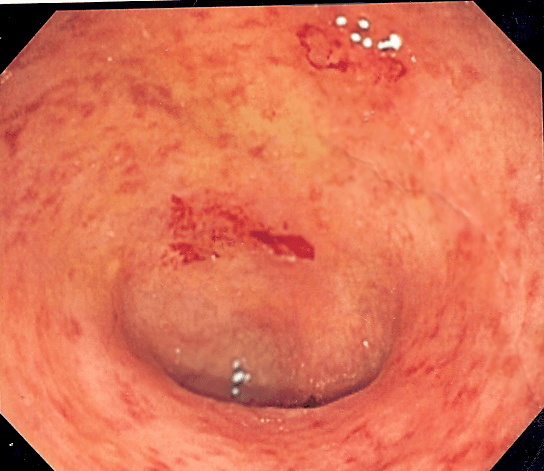

La rectocolite hémorragique (RCH) ou colite ulcéreuse est une maladie inflammatoire chronique intestinale (MICI) qui affecte l'extrémité distale du tube digestif, c’est-à-dire le côlon et le rectum qui est toujours touché. Son étiologie est inconnue, bien qu'une composante génétique constitue une hypothèse. Elle est classée dans les maladies auto-immunes. C'est une maladie qui agit par poussée et qui ne se guérit pas, ce qui nécessite un traitement médicamenteux à vie. L'objectif des traitements est que les rémissions durent le plus longtemps possible. Son diagnostic repose essentiellement sur les examens cytologiques qui accompagnent les prélèvements lors d'une coloscopie. Tout comme la maladie de Crohn, elle peut s'accompagner de manifestations extra-intestinales : articulaires, cutanées, oculaires Les malades atteints de RCH ou de la maladie de Crohn sont parfois sujets à la laxophobie. La maladie évolue par poussées inflammatoires de la muqueuse du côlon, qui peuvent durer des mois et se répéter plusieurs fois par an, entrecoupées de période d'accalmie. Le diagnostic de la RCH est posé sur un ensemble d'éléments cliniques et paracliniques. Le tableau clinique regroupe des signes digestifs et des signes extradigestifs. Les symptômes digestifs sont principalement constitués d'une diarrhée chronique et sanglante (plusieurs semaines à plusieurs mois), hémorragique dans les poussées graves, très douloureuse et accompagnée fréquemment de glaires mélangées ou non aux selles. Les patients souffrent de brulures rectales (ténesme), de coliques expulsives et d'épreintes (faux besoins). Il peut exister des manifestations extra-intestinales, principalement ostéoarticulaires (rhumatisme axial et périphérique) mais aussi hépatobiliaires (cholangites sclérosantes primitives), oculaires (conjonctivites et uvéites) ou cutanées (aphtes buccaux, érythèmes noueux, pyoderma gangrenosum). La fatigue est un symptôme classique, présent même en dehors des poussées. Les poussées sévères s'accompagnent fréquemment d'amaigrissement, d'anémie et/ou de fièvre.